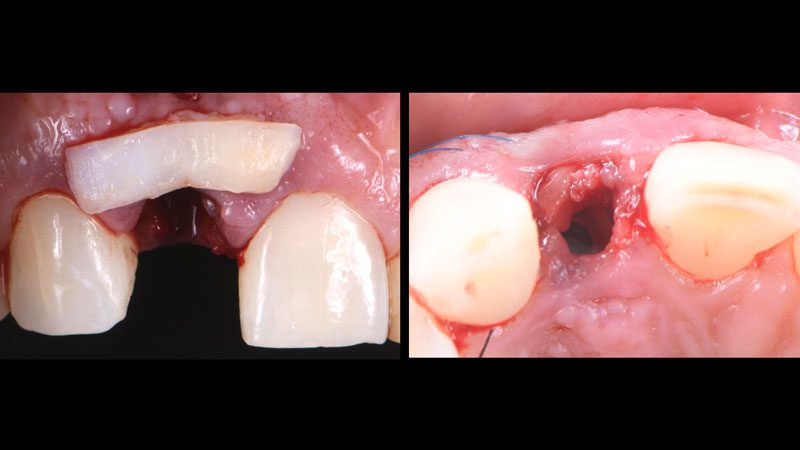

Hình 2. Nhổ răng sang chấn tối thiểu bằng hệ thống Benex để bảo vệ xương và mô mềm xung quanh.

Hệ thống nhổ răng không sang chấn Benex.

Hình 7. Ghép mô mềm (lấy mô từ khẩu cái) bằng kĩ thuật đường hầm (tunneling technique).

Hình 8. Ghép Collagen BioOss vào vùng thiếu hổng, đặt trụ Healing cá nhân. Sau khi gắn phục hình tạm (cầu dán Maryland) thì thêm 2 mũi khâu treo xung quanh để nâng đỡ cho mô ghép.